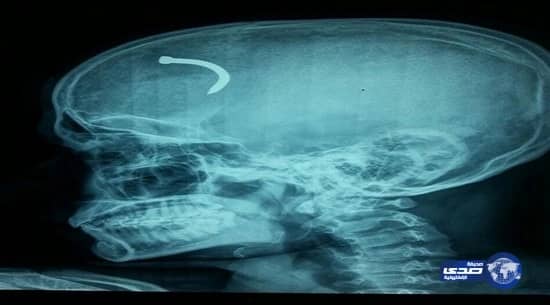

أجريت جراحة ناجحة لمقيم هندي بمستشفى الأمير عبدالعزيز بن مساعد بمدينة عرعر في أعقاب اختراق مسمار جداري عظام الجمجمة ليستقر بعدها في أنشطة الدماغ.

اتضح أن المريض يعمل بالخازق الكهربائي ووضع مسمارًا في الجدار فاختل توازنه وحدث ارتداد قوي للجهاز أدى إلى انعكاس المسمار الجداري واخترق عظام الجمجمة من الجبهة ناحية الجهة اليمنى فوق حجاب العين واستقر في أنشطة الدماغ.

يذكر أن الطبيب الذي باشر الجراحة هو الدكتور محمد جهانقير استشاري جراحة المخ والأعصاب والذي قام بفتح عظام الجمجمة وأزال المسمار من أغشية الدماغ الداخلية.

صرح بذلك المتحدث باسم صحة منطقة الحدود الشمالية أحمد أمان والذي أضاف أن العمليه قد تكللت بالنجاح وخرج المريض من المستشفى بصحة ممتازة دون ترك أي آثار جانبية جسدية أو ذهنية.